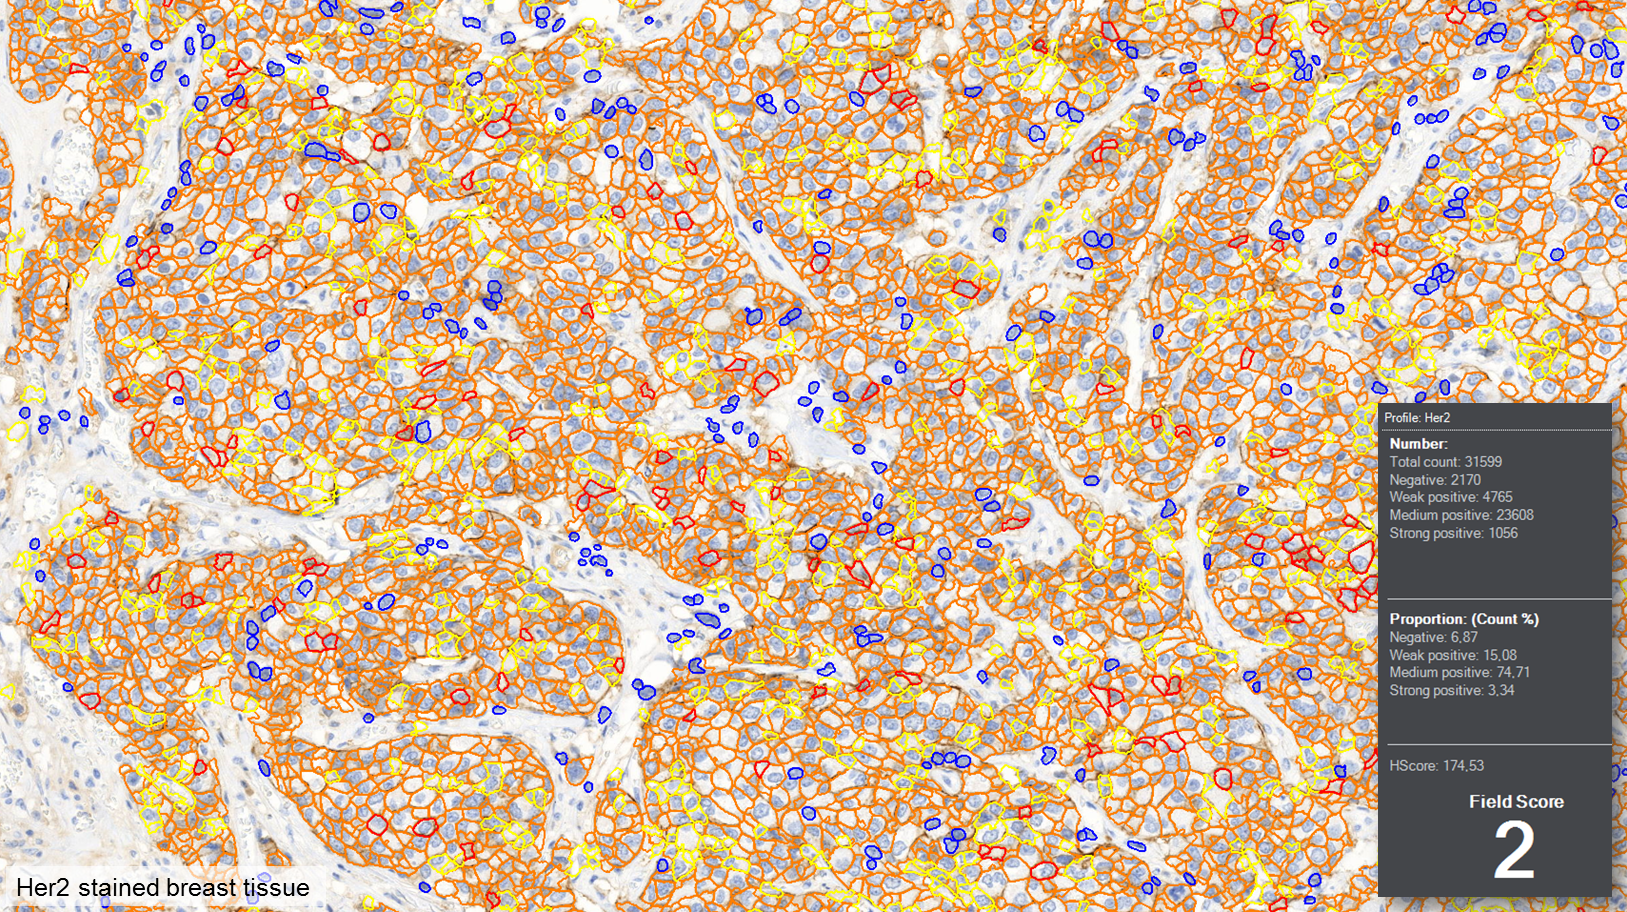

MembraneQuant is a cell membrane detection software application that can be used for the quantification of IHC stained histological samples. This module measures cell morphology and stain density, reports intensity-based core ranges, overall scores and positivity percentages (including H-Score), distinguishing the continuous membrane stain from the moderate stain.

This module has IVD approval for the quantification of Her2 expression in breast tissue samples.